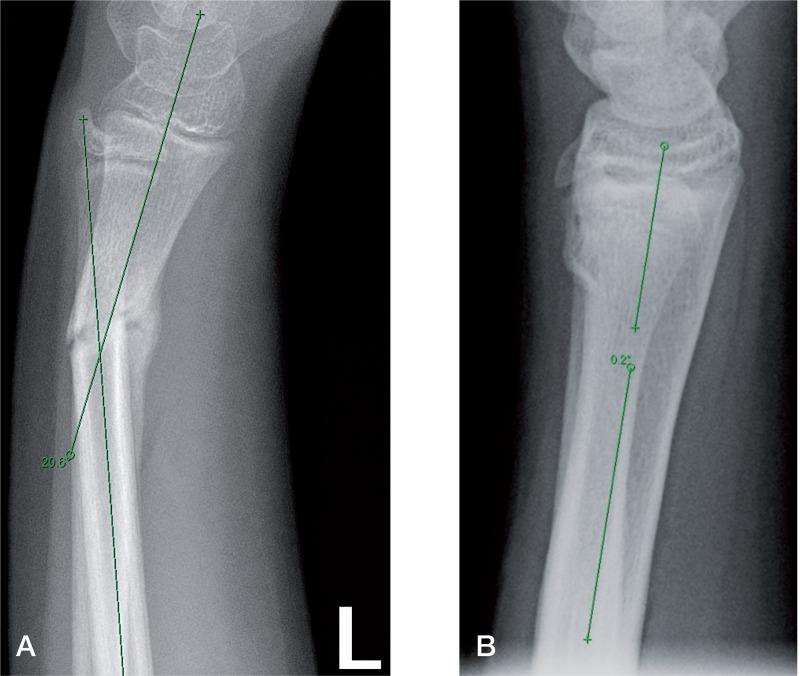

Distal forearm fractures in children have excellent remodeling potential. The current literature states that 15° is the maximum acceptable angulation limit, though studies focusing on remodeling capacity above this value are lacking. We present data on the remodeling process in children with distal radius malunions with an angulation of ≥ 15°.

Retrospectively, we radiographically evaluated the remodeling in 33 children (aged 3-14 years) with 40 distal radius fractures healed in ≥ 15° angulation in the dorsovolar (DV) plane (n = 32) and/or the radioulnar (RU) plane (n = 8). Malunion angulation at the start and at last follow-up was measured on AP and lateral-view radiographs. Mean follow-up time was 9 (3-29) months.

All fractures showed remodeling. Mean DV malunion angulation was 23° (15-49) and mean RU malunion angulation was 21° (15-33). At follow-up, this had remodeled to mean 8° (-2 to 21) DV and 10° (3-17) RU. Mean remodeling speed (RS) was 2.5° (0.4-7.6) per month. There was a negative correlation between RS and remodeling time (RT) and a positive correlation between RS and malunion angulation. The relationship between RS and RT was exponential. RS was not found to be related to age or sex.

儿童前臂远端骨折具有良好的重塑潜力。当前文献表明,15°是可接受的最大成角限度,不过缺乏针对超过此值的重塑能力的研究。我们呈现了桡骨远端畸形愈合且成角≥15°的儿童重塑过程的数据。

患者与方法

我们回顾性地对33名年龄在3至14岁的儿童进行了影像学评估,这些儿童的40例桡骨远端骨折在背掌侧(DV)平面(n = 32)和/或桡尺侧(RU)平面(n = 8)以≥15°的角度愈合。在前后位和侧位X线片上测量初始和末次随访时的畸形愈合角度。平均随访时间为9(3 - 29)个月。

结果

所有骨折均显示出重塑。平均DV畸形愈合角度为23°(15 - 49),平均RU畸形愈合角度为21°(15 - 33)。在随访时,这已重塑至平均DV为8°(-2至21),RU为10°(3 - 17)。平均重塑速度(RS)为每月2.5°(0.4 - 7.6)。RS与重塑时间(RT)呈负相关,与畸形愈合角度呈正相关。RS与RT之间的关系呈指数关系。未发现RS与年龄或性别有关。